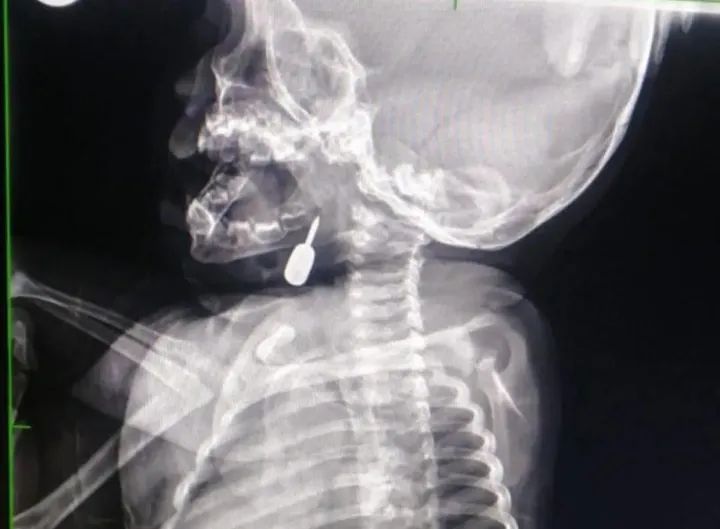

إنقاذ حياة طفل يبلغ 11 شهرًا بعملية فتح رُغامي هي الأولى من نوعها في مستشفى الملكة رانيا تمكّن أخصائي الأنف والأذن والحنجرة الدكتور محمود السبول من...